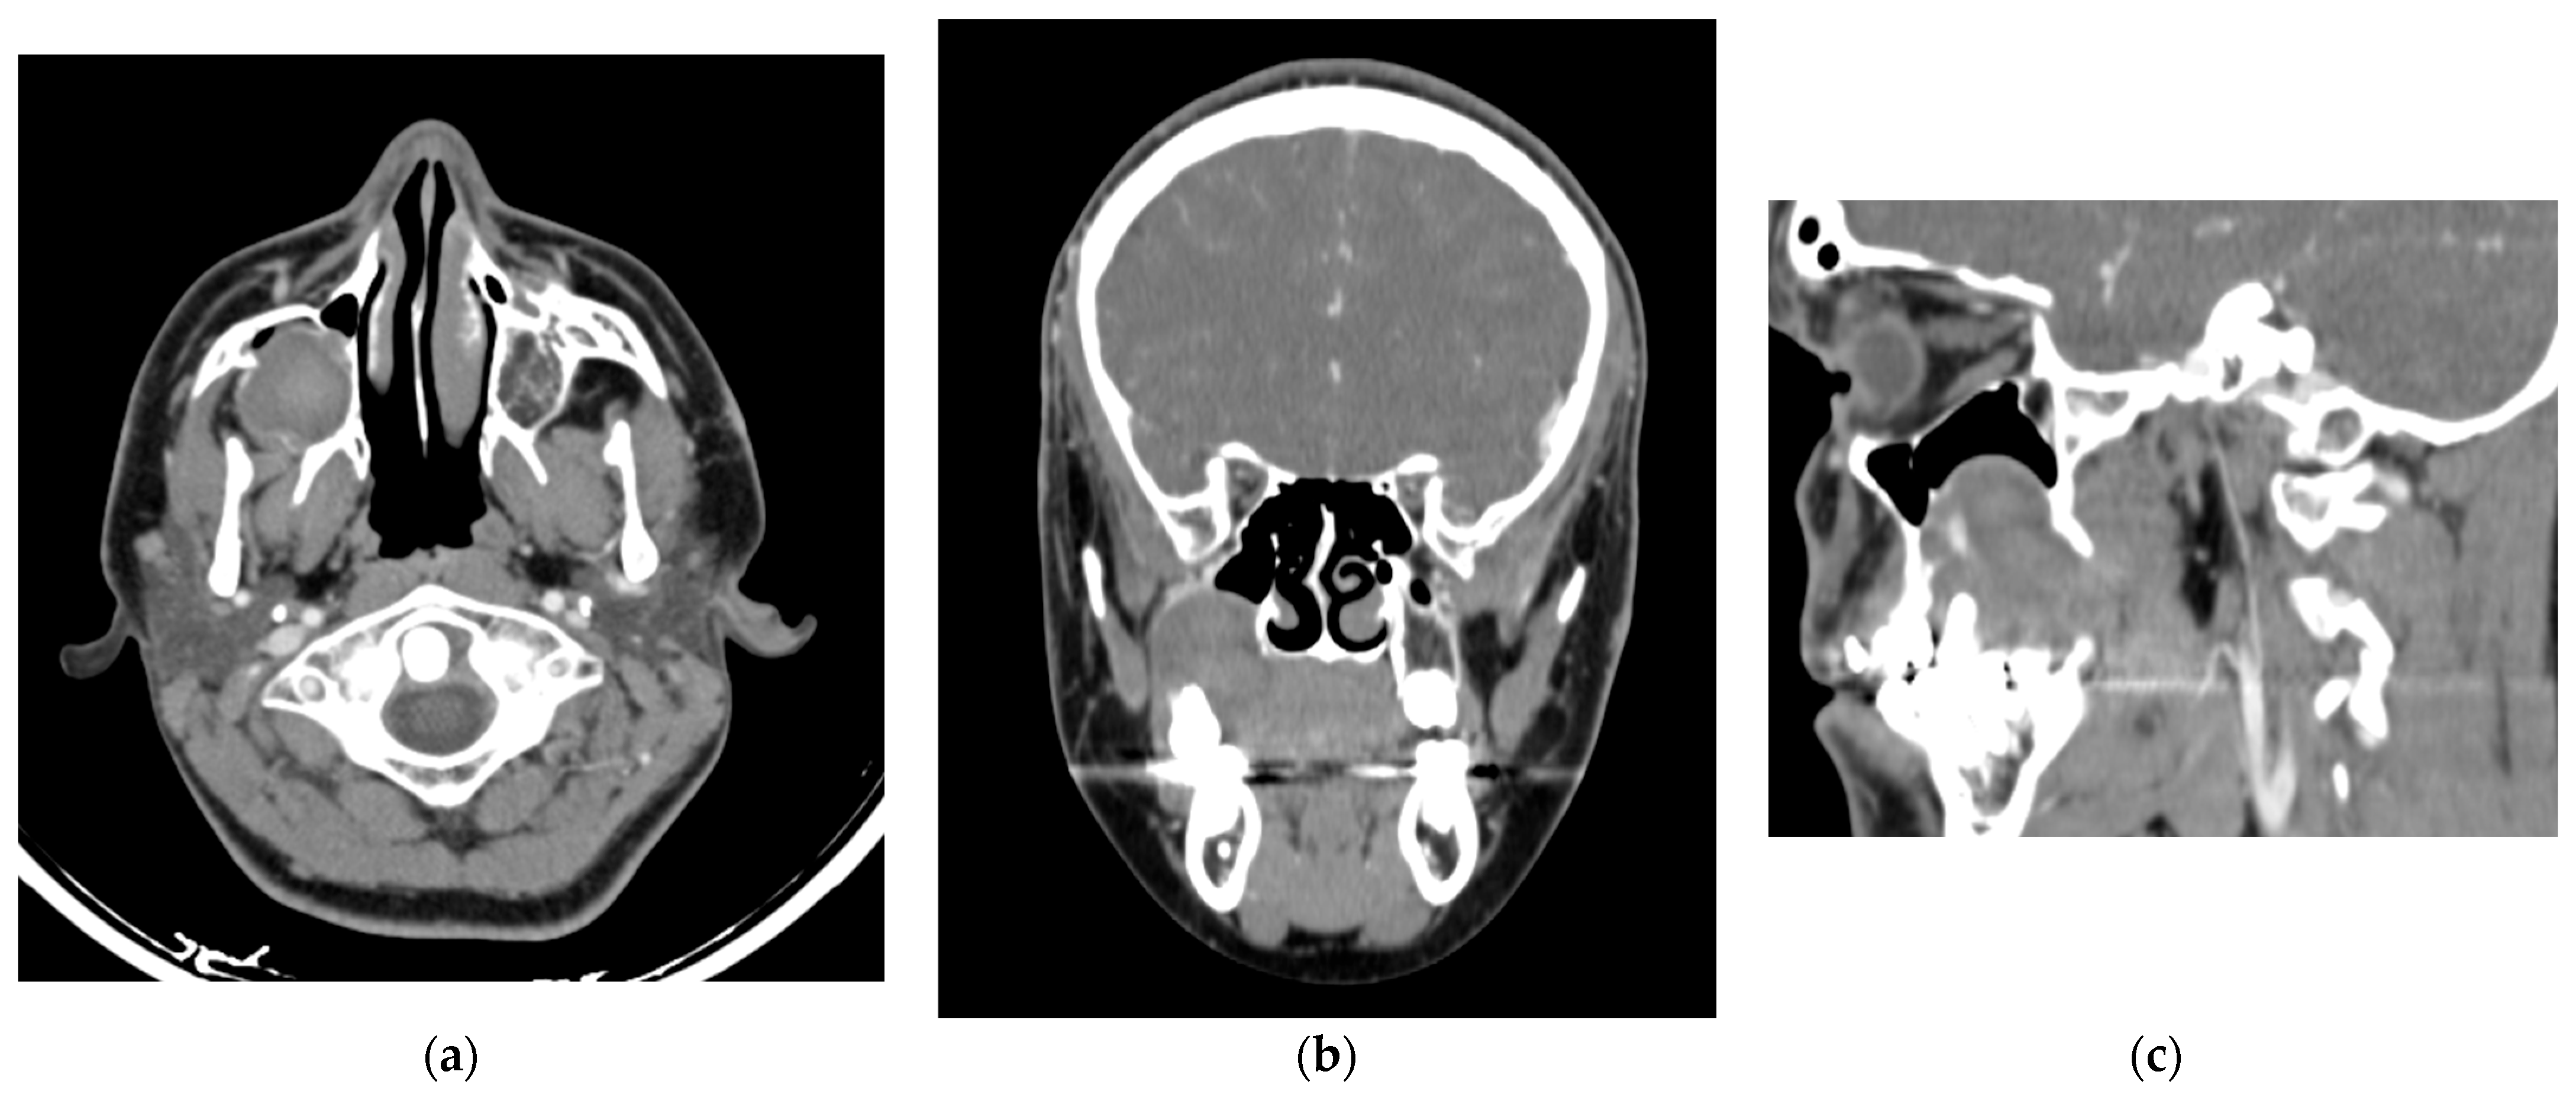

Figure 3.

Contrast-enhanced computed tomography (a) Three-dimensional reconstruction with MIP mask showing the endodontic treatment performed on the upper first molar. (b) Three-dimensional reconstruction showing bone loss/erosion in the right maxilla, primarily affecting the molars.